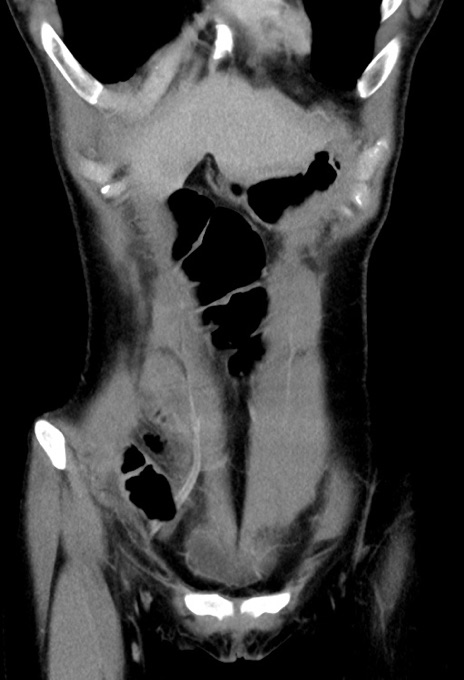

症例17(冠状断像)

【症例】20歳代女性

【主訴】嘔吐、下腹部痛

【現病歴】昨日夕食後に嘔吐し下腹部痛が出現。本日になっても嘔吐持続し改善しないため来院。

【身体所見】意識清明、BT 37.2℃、BP 108/67mmHg、腹部:平坦、やや硬、下腹部正中から右にかけて圧痛あり、反跳痛軽度あり、tapping pain(+)。

【データ】WBC 13600、CRP 14.94